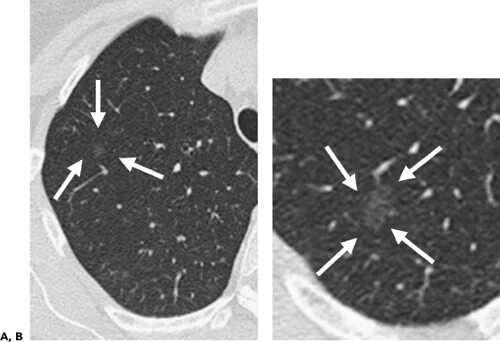

Участок уплотнения по типу матового стекла